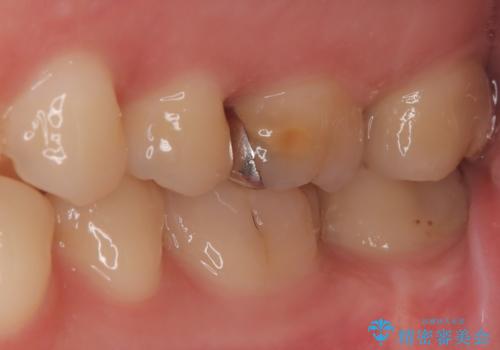

部分的断髄法(MTAの使用): ラバーダム防湿を行い、無菌的な環境下で虫歯を慎重に除去。神経の露出を確認した後、炎症を起こしている一部の神経のみを除去し、残りの健全な神経を保護するためにMTAセメントを充填しました。これにより、神経の機能を維持し、歯を内部から守ることが可能となりました。

経過観察と土台作り: 一定期間の経過を観察し、痛みや炎症がないことを確認。神経の生存を確認した上で、セラミックを支えるための土台を精密に構築しました。